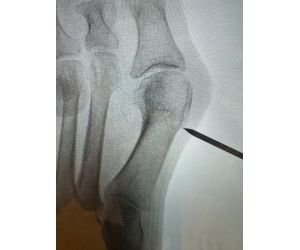

How Would You Fix This?

Michael A Campbell, MD

All right LinkedIn foot and ankle/trauma peeps…. What would you do? 58 y/o male. NIDDM, mild neuropathy and HTN. No insurance so limited medical...